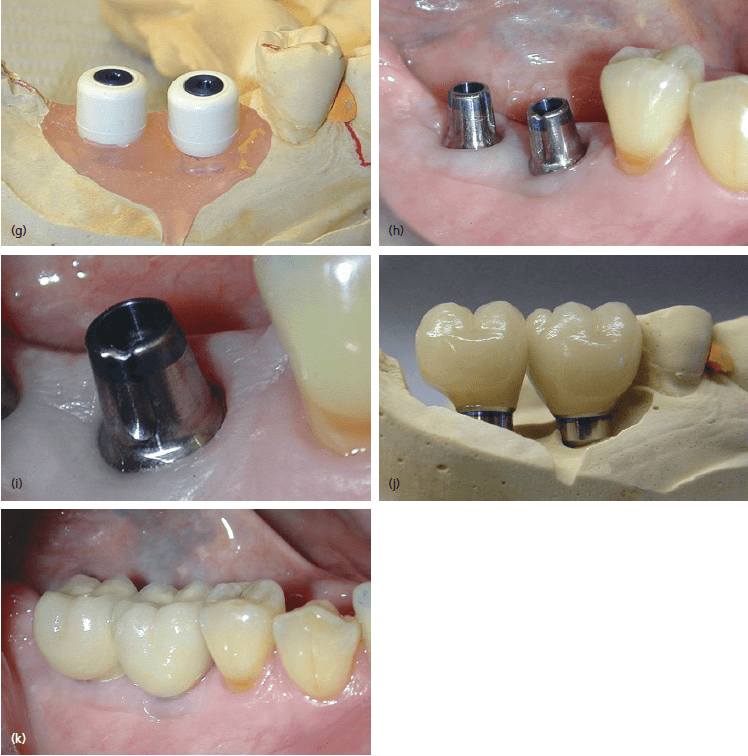

Современные коронки на зубные импланты: виды и фото-примеры